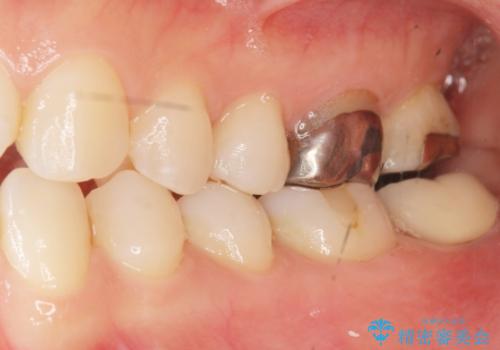

割れている奥歯を抜去後左上の機能していない親知らずを移植し、生着したのち根管治療・補綴を行いました。

インプラントや義歯を用いることなく咬合を回復することができ、喜んで頂けました。

治療期間も抜歯後3ヶ月以内かつ少ない来院回数(初診含めて6回)で治療を終えることができ、ご満足頂けました。

被せ物の種類:メタルボンドクラウン エコノミー フルベイク